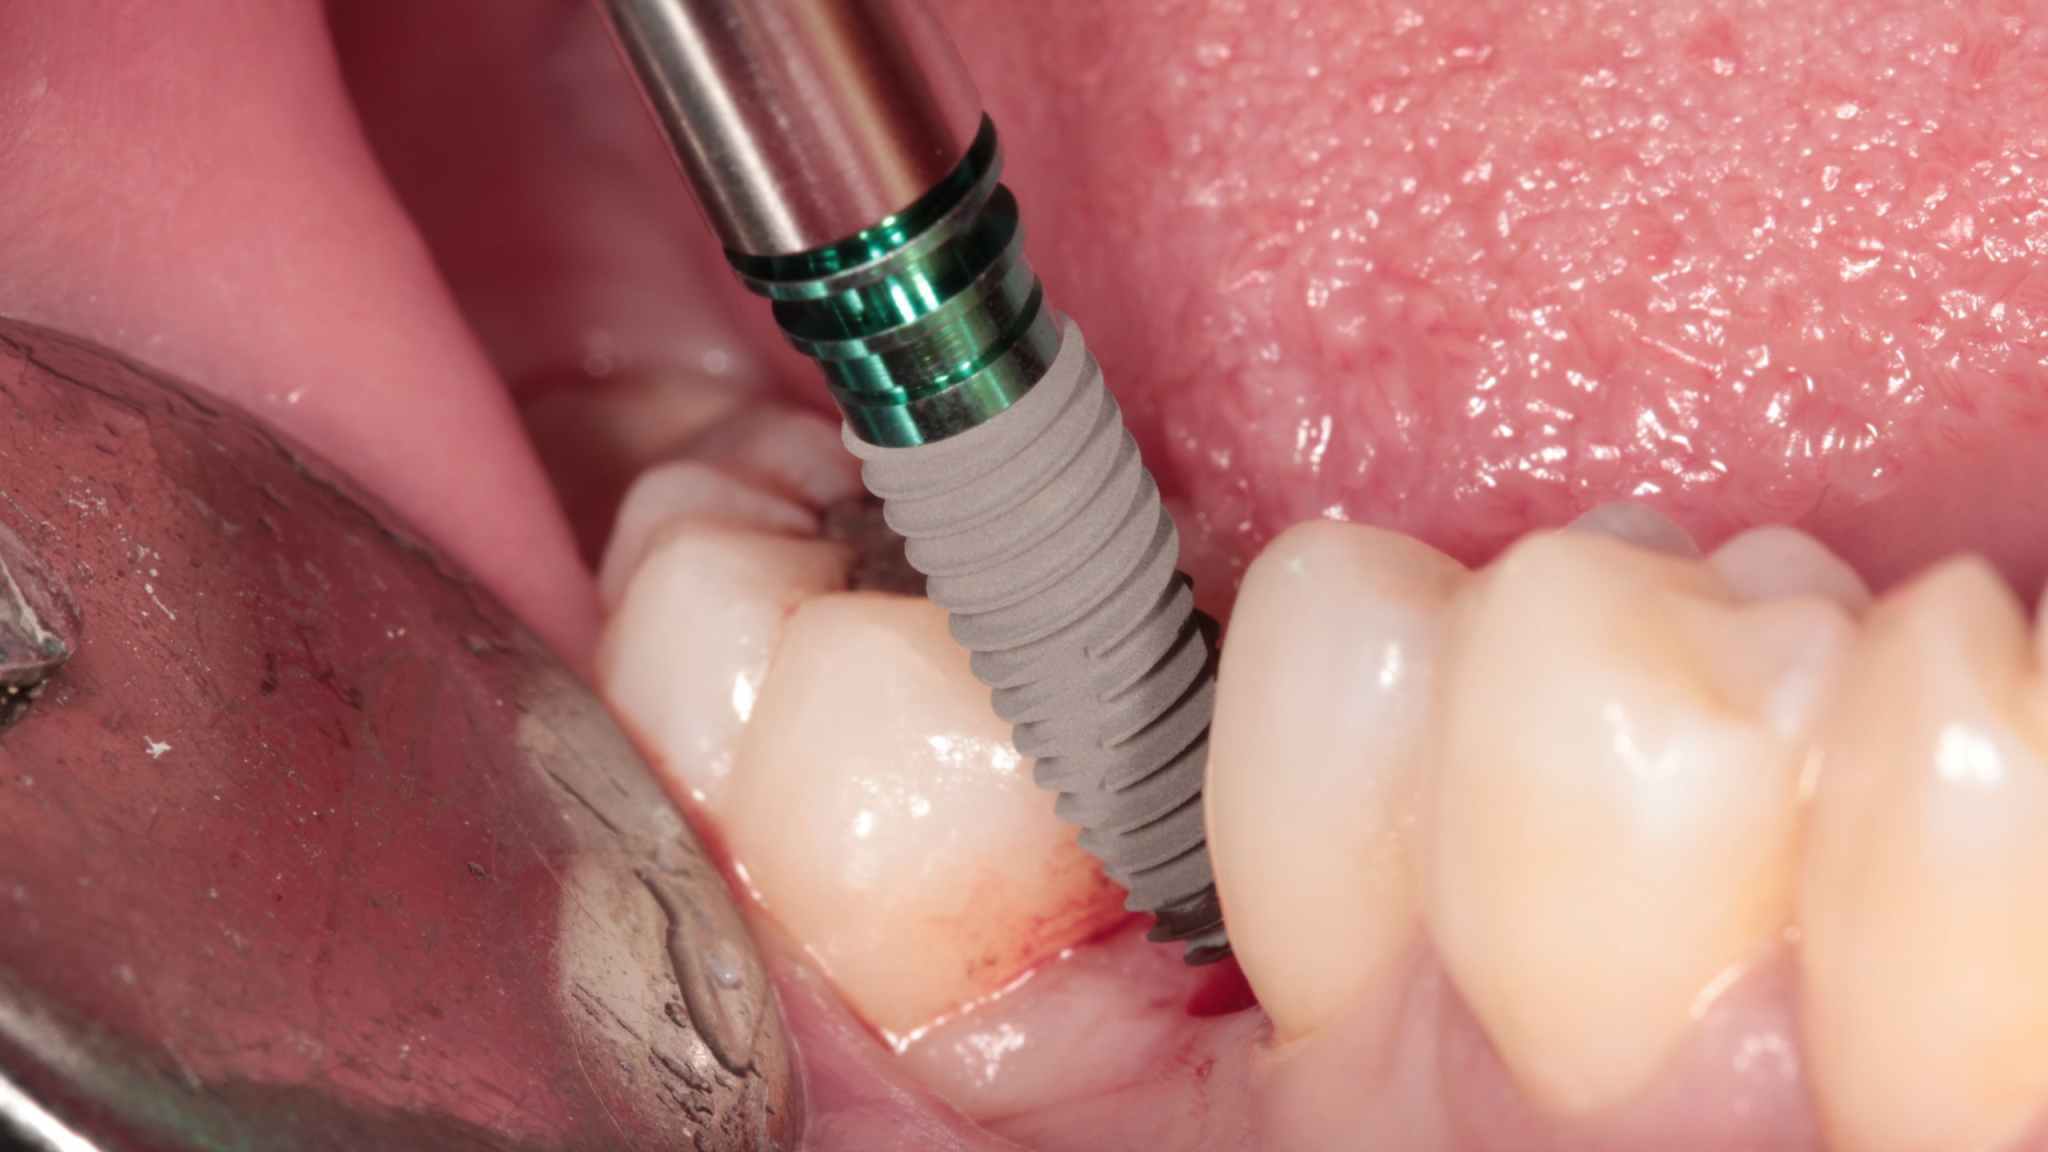

5. Surgical procedure

Position the surgical guide, then incise gingiva and drill pilot hole. Check depth and condition of pilot hole.

Profile drill for implant. Insert the implant.